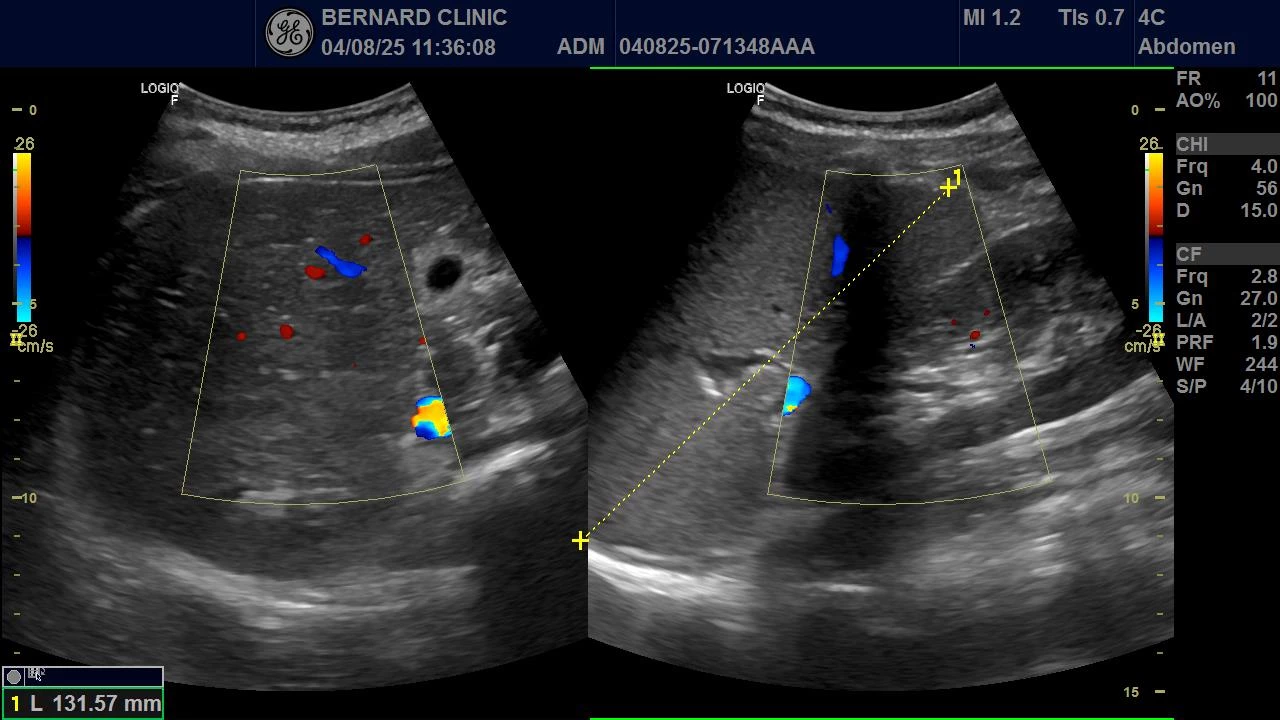

Bên cạnh đó, hình ảnh siêu âm bụng của bệnh nhi A cho thấy lách to độ I (69 × 131 mm).